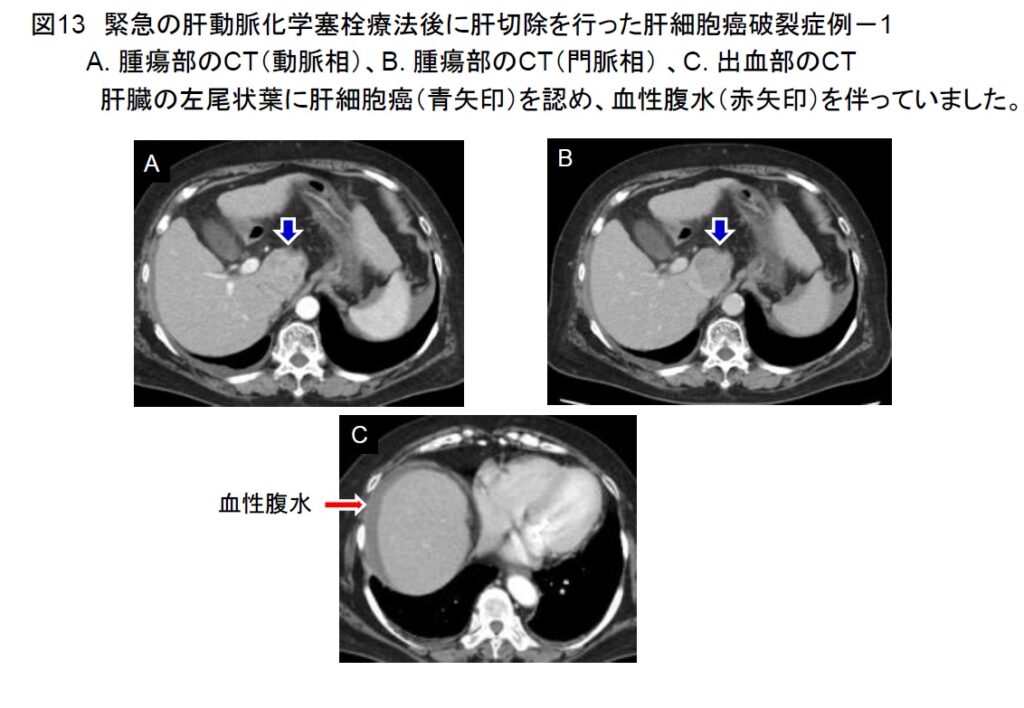

2017年に腹腔鏡肝切除の施設認定を取得し、高難度手術を含めた腹腔鏡肝切除を積極的に行っています(図12)。その他に肝切除例としては、緊急の肝動脈化学塞栓療法後に肝切除を行った症例(図13-16)や門脈塞栓術後に肝切除を行った大型肝細胞癌症例を経験しました(図17-19)。いずれも経過は極めて良好です。肝切除の適応決定時には、3次元画像解析シナプスVINCENTTMによる肝体積評価やアシアロSPECT-CT 融合画像による機能的肝体積評価を行い、より安全な手術を目指しています(図20)。